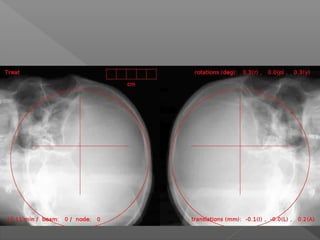

MMCP 46años. Ca de mama, RT

Holocraneal previa

Radiocirugia con RC

12 03 2013 16/01/2013

septiembre 2012

MTL 67 años metastasis unica subependimaria. 3 meses

despues de radicirugia 24Gy una fraccion-

FGV linfoma del MantoOctubre 2013

9 meses posradiocirugia